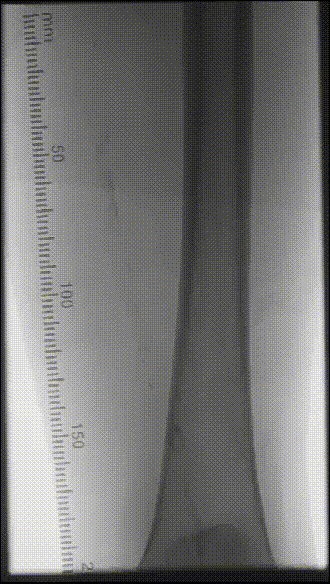

CTA:左侧股总动脉高钙化性偏心性严重狭窄病变,左股浅动脉及腘动脉全程弥漫性钙化病变,节段性狭窄,股浅动脉远段至腘动脉P1段完全闭塞,左侧胫前动脉至足背动脉闭塞

ABI:左侧0.37,右侧0.81

根据PACSS 透视/DSA下钙化分级属于PACSS Grade 4C